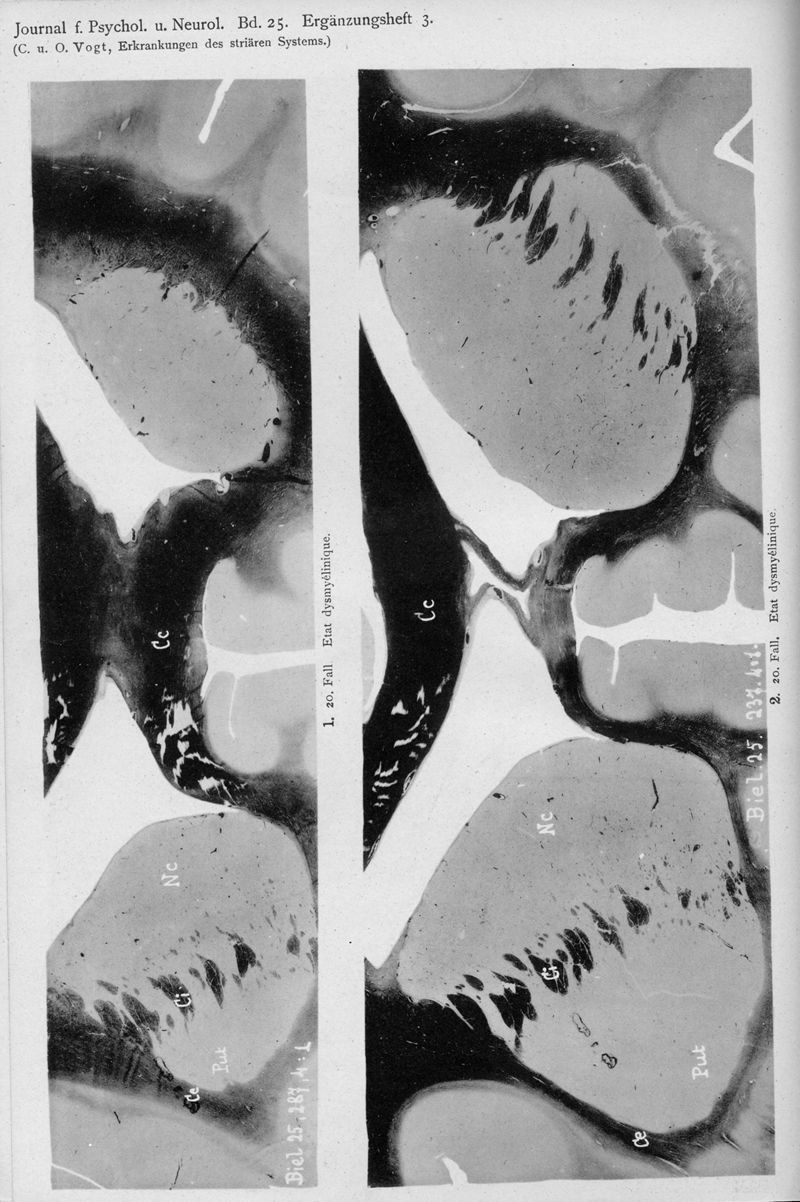

VOGT, Cécile / VOGT, O.

In : Journal für Psychologie und Neurologie,

1920, Vol. 25, pp. 627-846